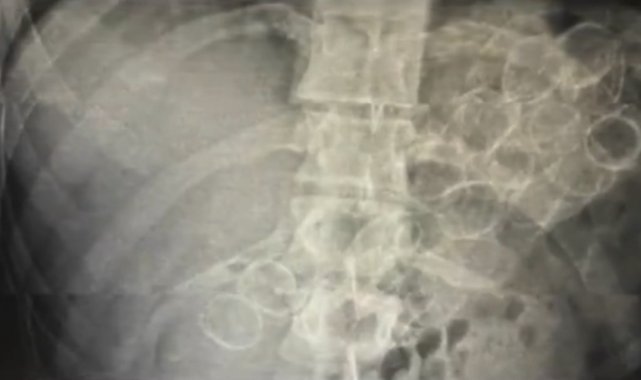

Bingöl İl Emniyet Müdürlüğü Narkotik Suçlarla Mücadele Şube Müdürlüğü ekiplerince yürütülen çalışmalar neticesinde, "Uyuşturucu veya Uyarıcı Madde Ticareti" suçu kapsamında 3 şahsın "yutma ve tıkma" yöntemiyle mide ve bağırsaklarında yüklü miktarda uyuşturucu madde taşıyarak kente getirdiği belirlendi. Ekipler tarafından yakalanan şüphelilerin hastanede yapılan tedavileri sonucunda, toplam 75 kapsül halinde 775 gram metamfetamin maddesi ele geçirildi.

Mide ve bağırsaklarında uyuşturucu ele geçirilen 3 şüpheli tutuklandı